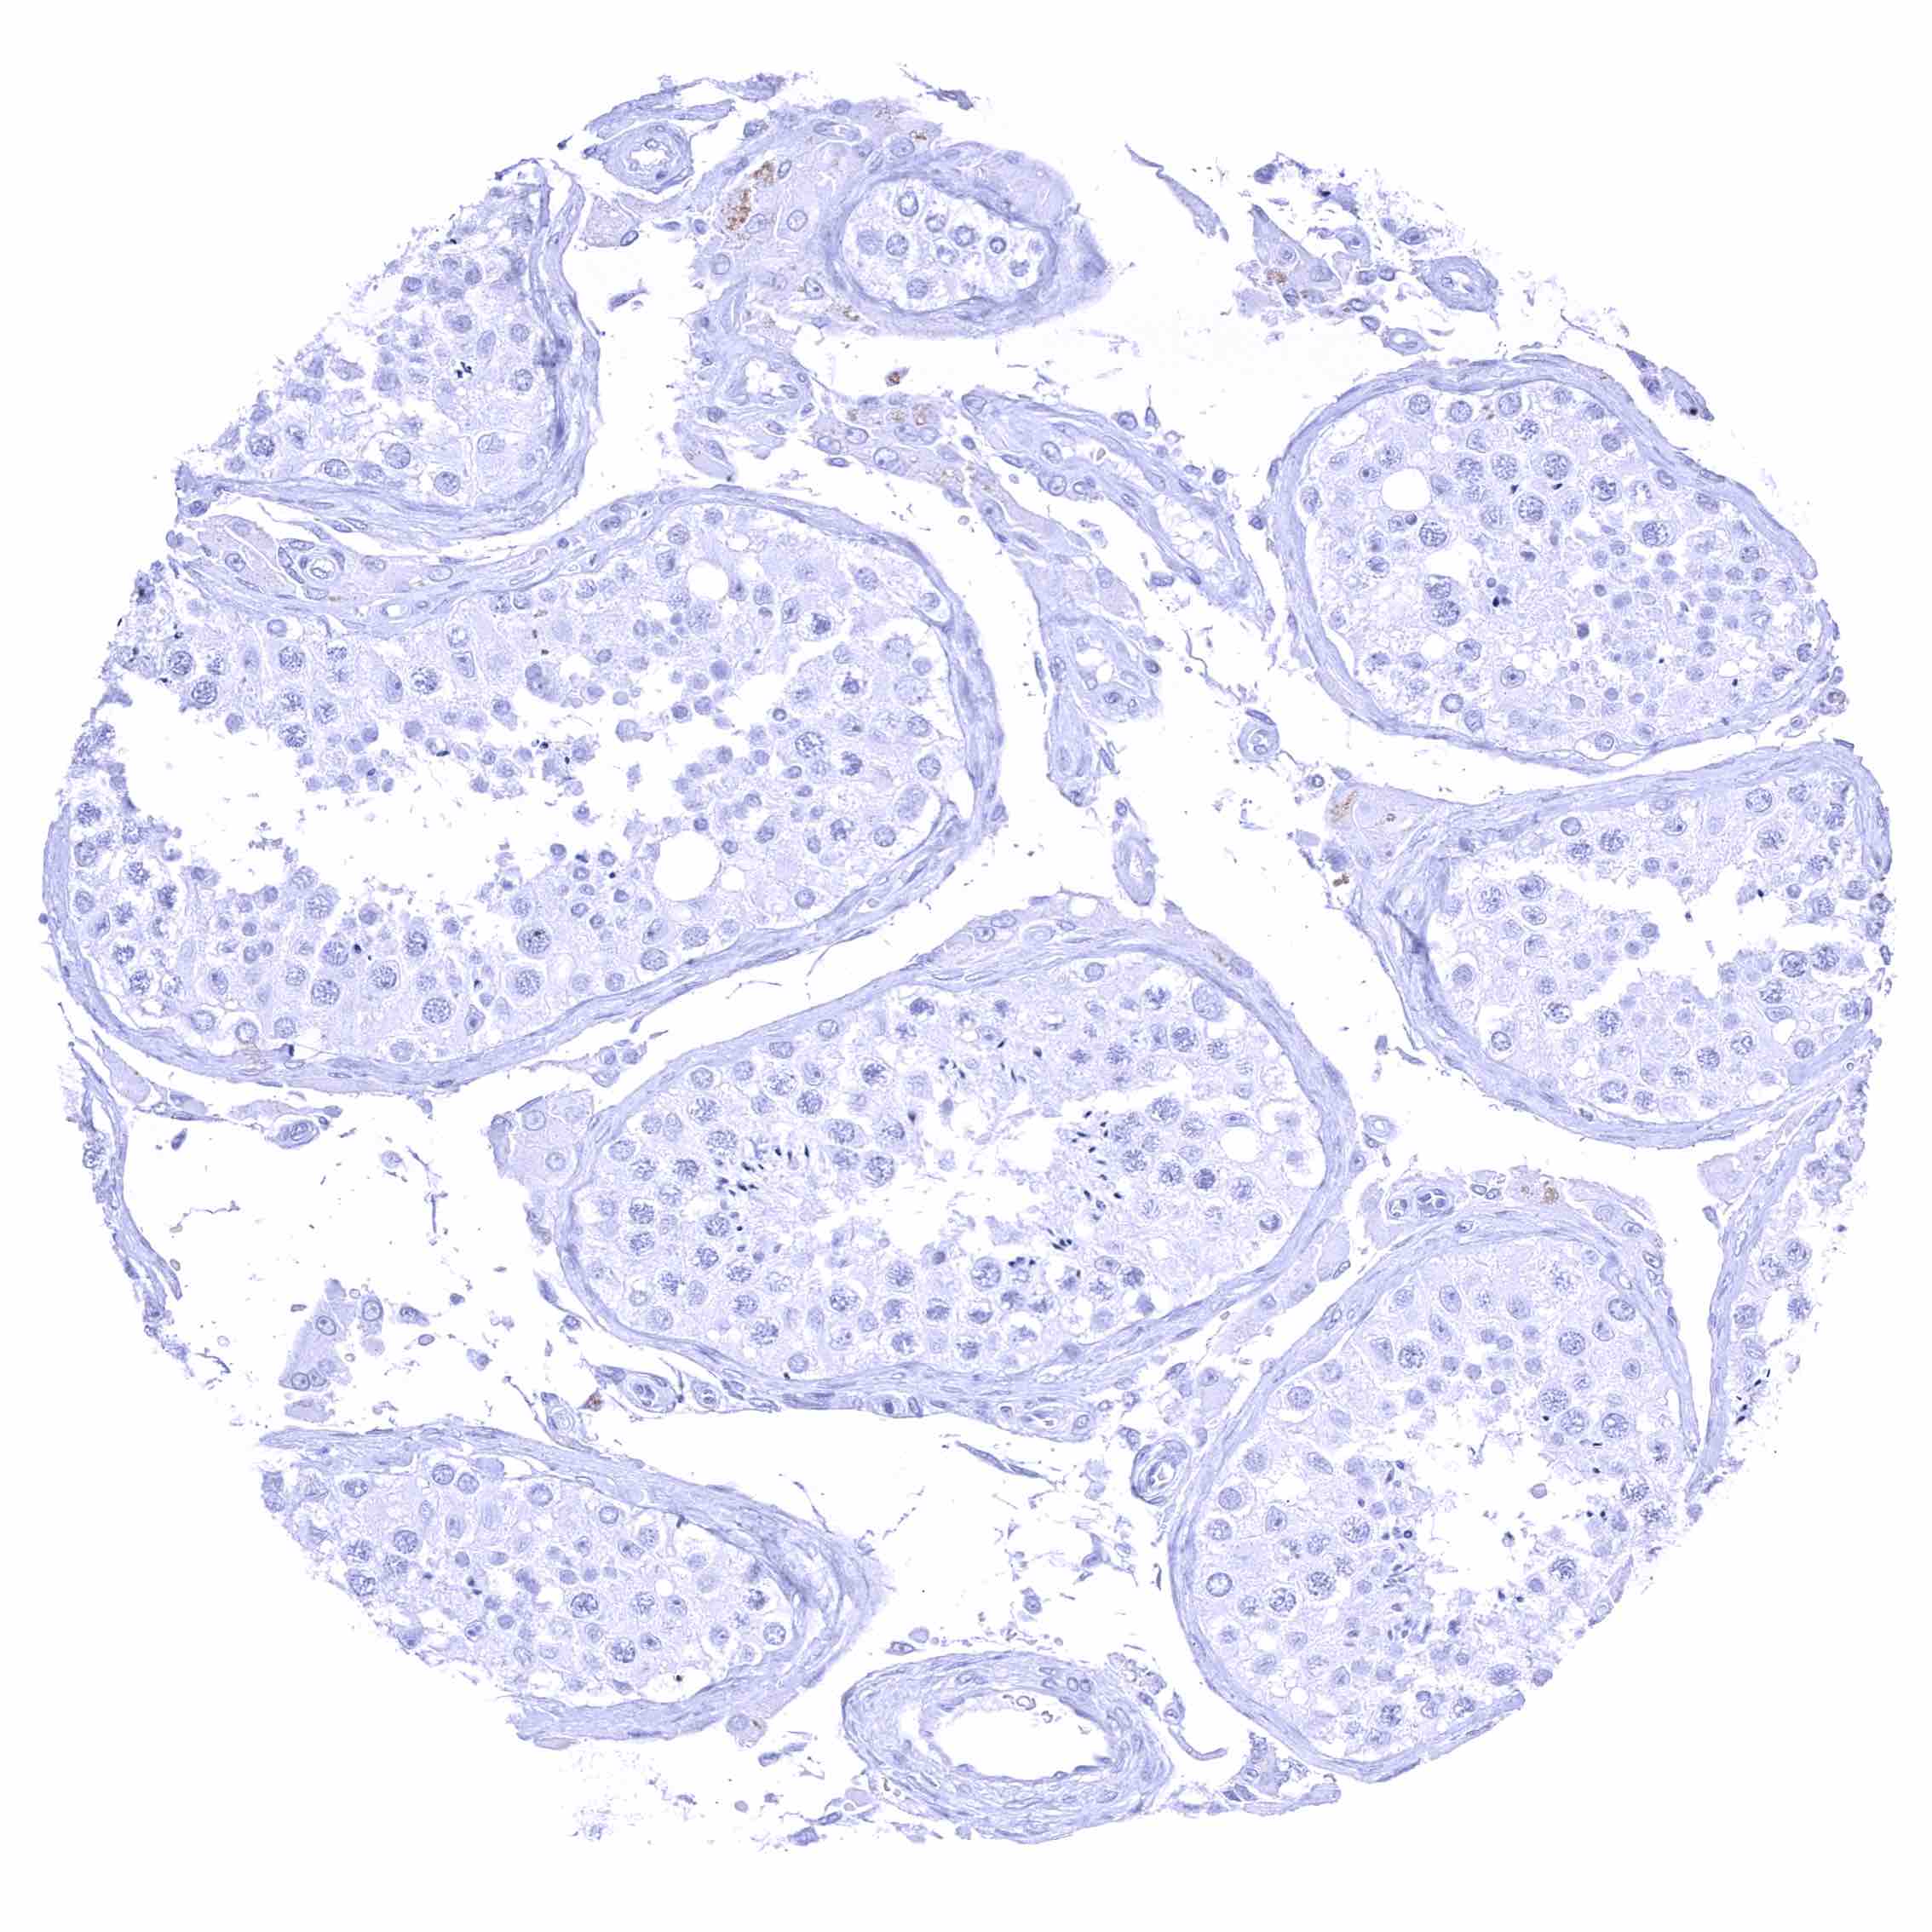

Testis